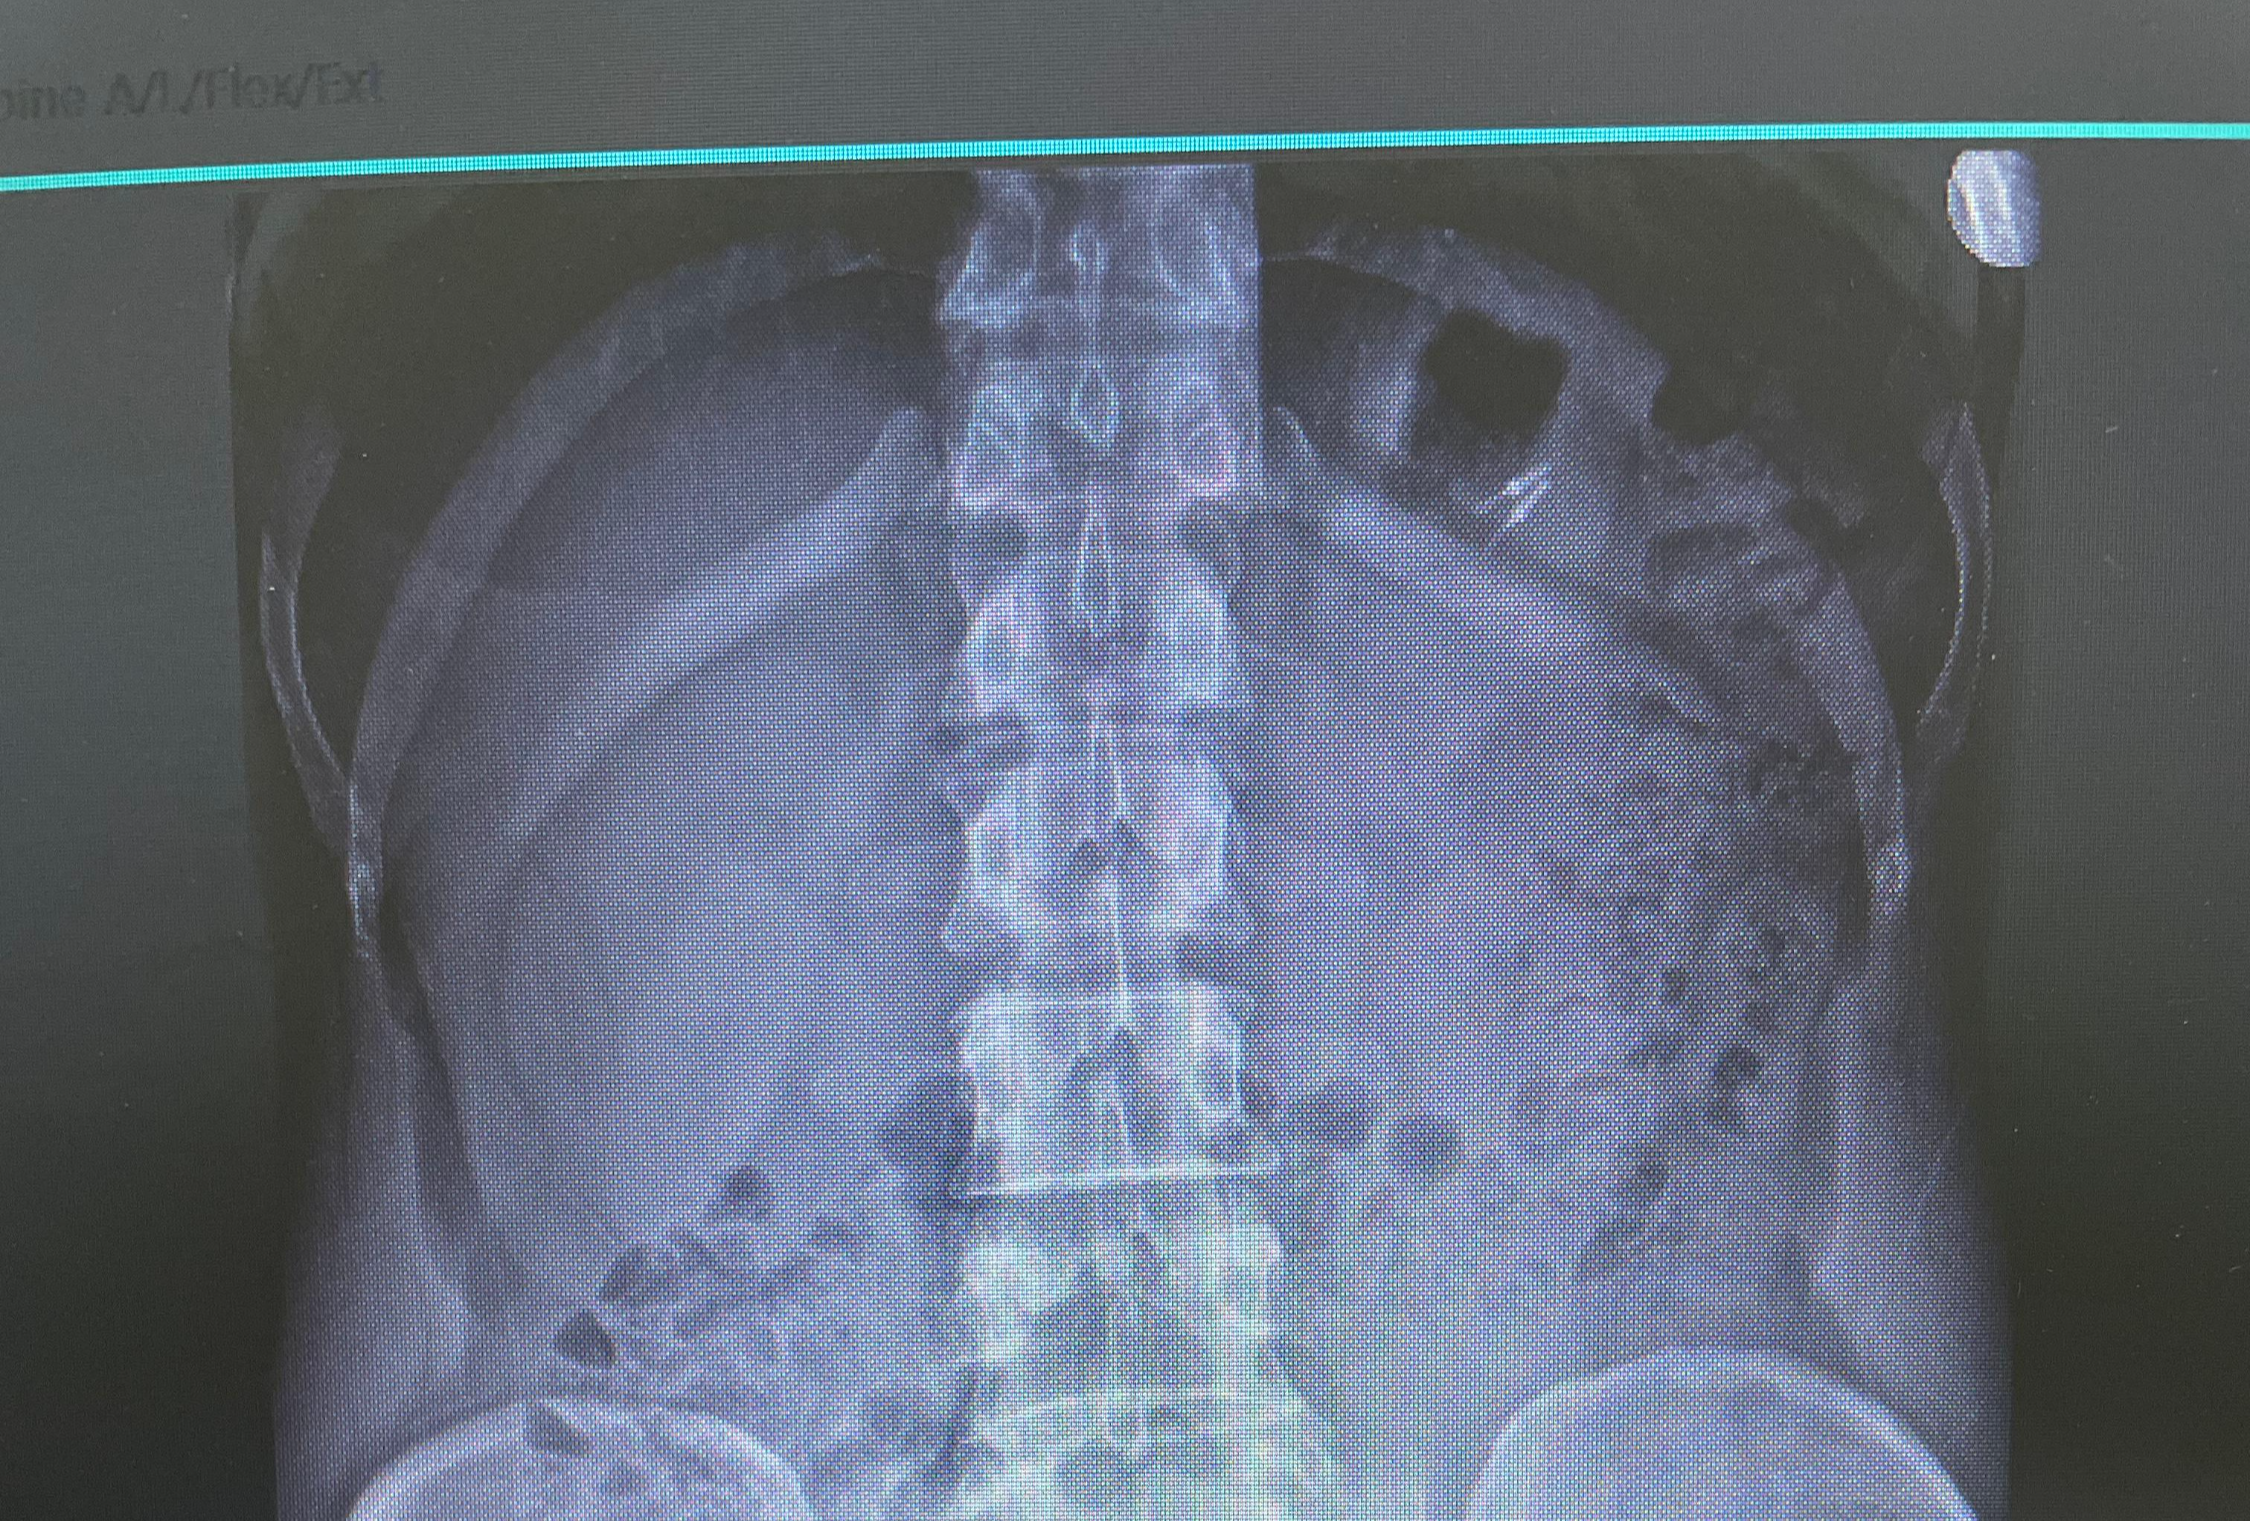

우연치않게 허리 사진을 찍어보다가 발견된 이상한 물질

폐 앞쪽으로 가슴쪽에 이상한? 물질이 찍혀있음.

옆으로 돌린 사진에도 나와 있음

아마도 내시경 할때에 용종 같은거 떼고나면 붙여놓는 클립처럼 보인다고.

22년도에 찍은 엑스레이 사진에도 떡하니 있다.

그것도 한개가 아닌 두개!!!!

주말에 지인 치과 병원 근무자를 만나서 물어봄

치과 치료용 파일이나 버

같아 보이기도 하는데